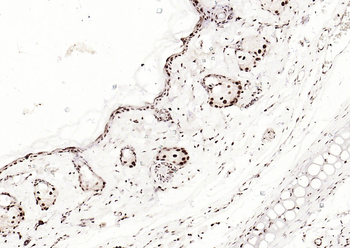

Phospho-Smad3 (Ser423 + Ser425) Rabbit Polyclonal Antibody [orb6983]

FC, IF, IHC-Fr, IHC-P, WB

Bovine, Canine, Equine, Gallus

Human, Mouse, Porcine, Rat

Rabbit

Polyclonal

Unconjugated

100 μl, 200 μl, 50 μlPhospho-SMAD5 (Ser463 + Ser465) Recombinant Rabbit Monoclonal Antibody [orb559123]